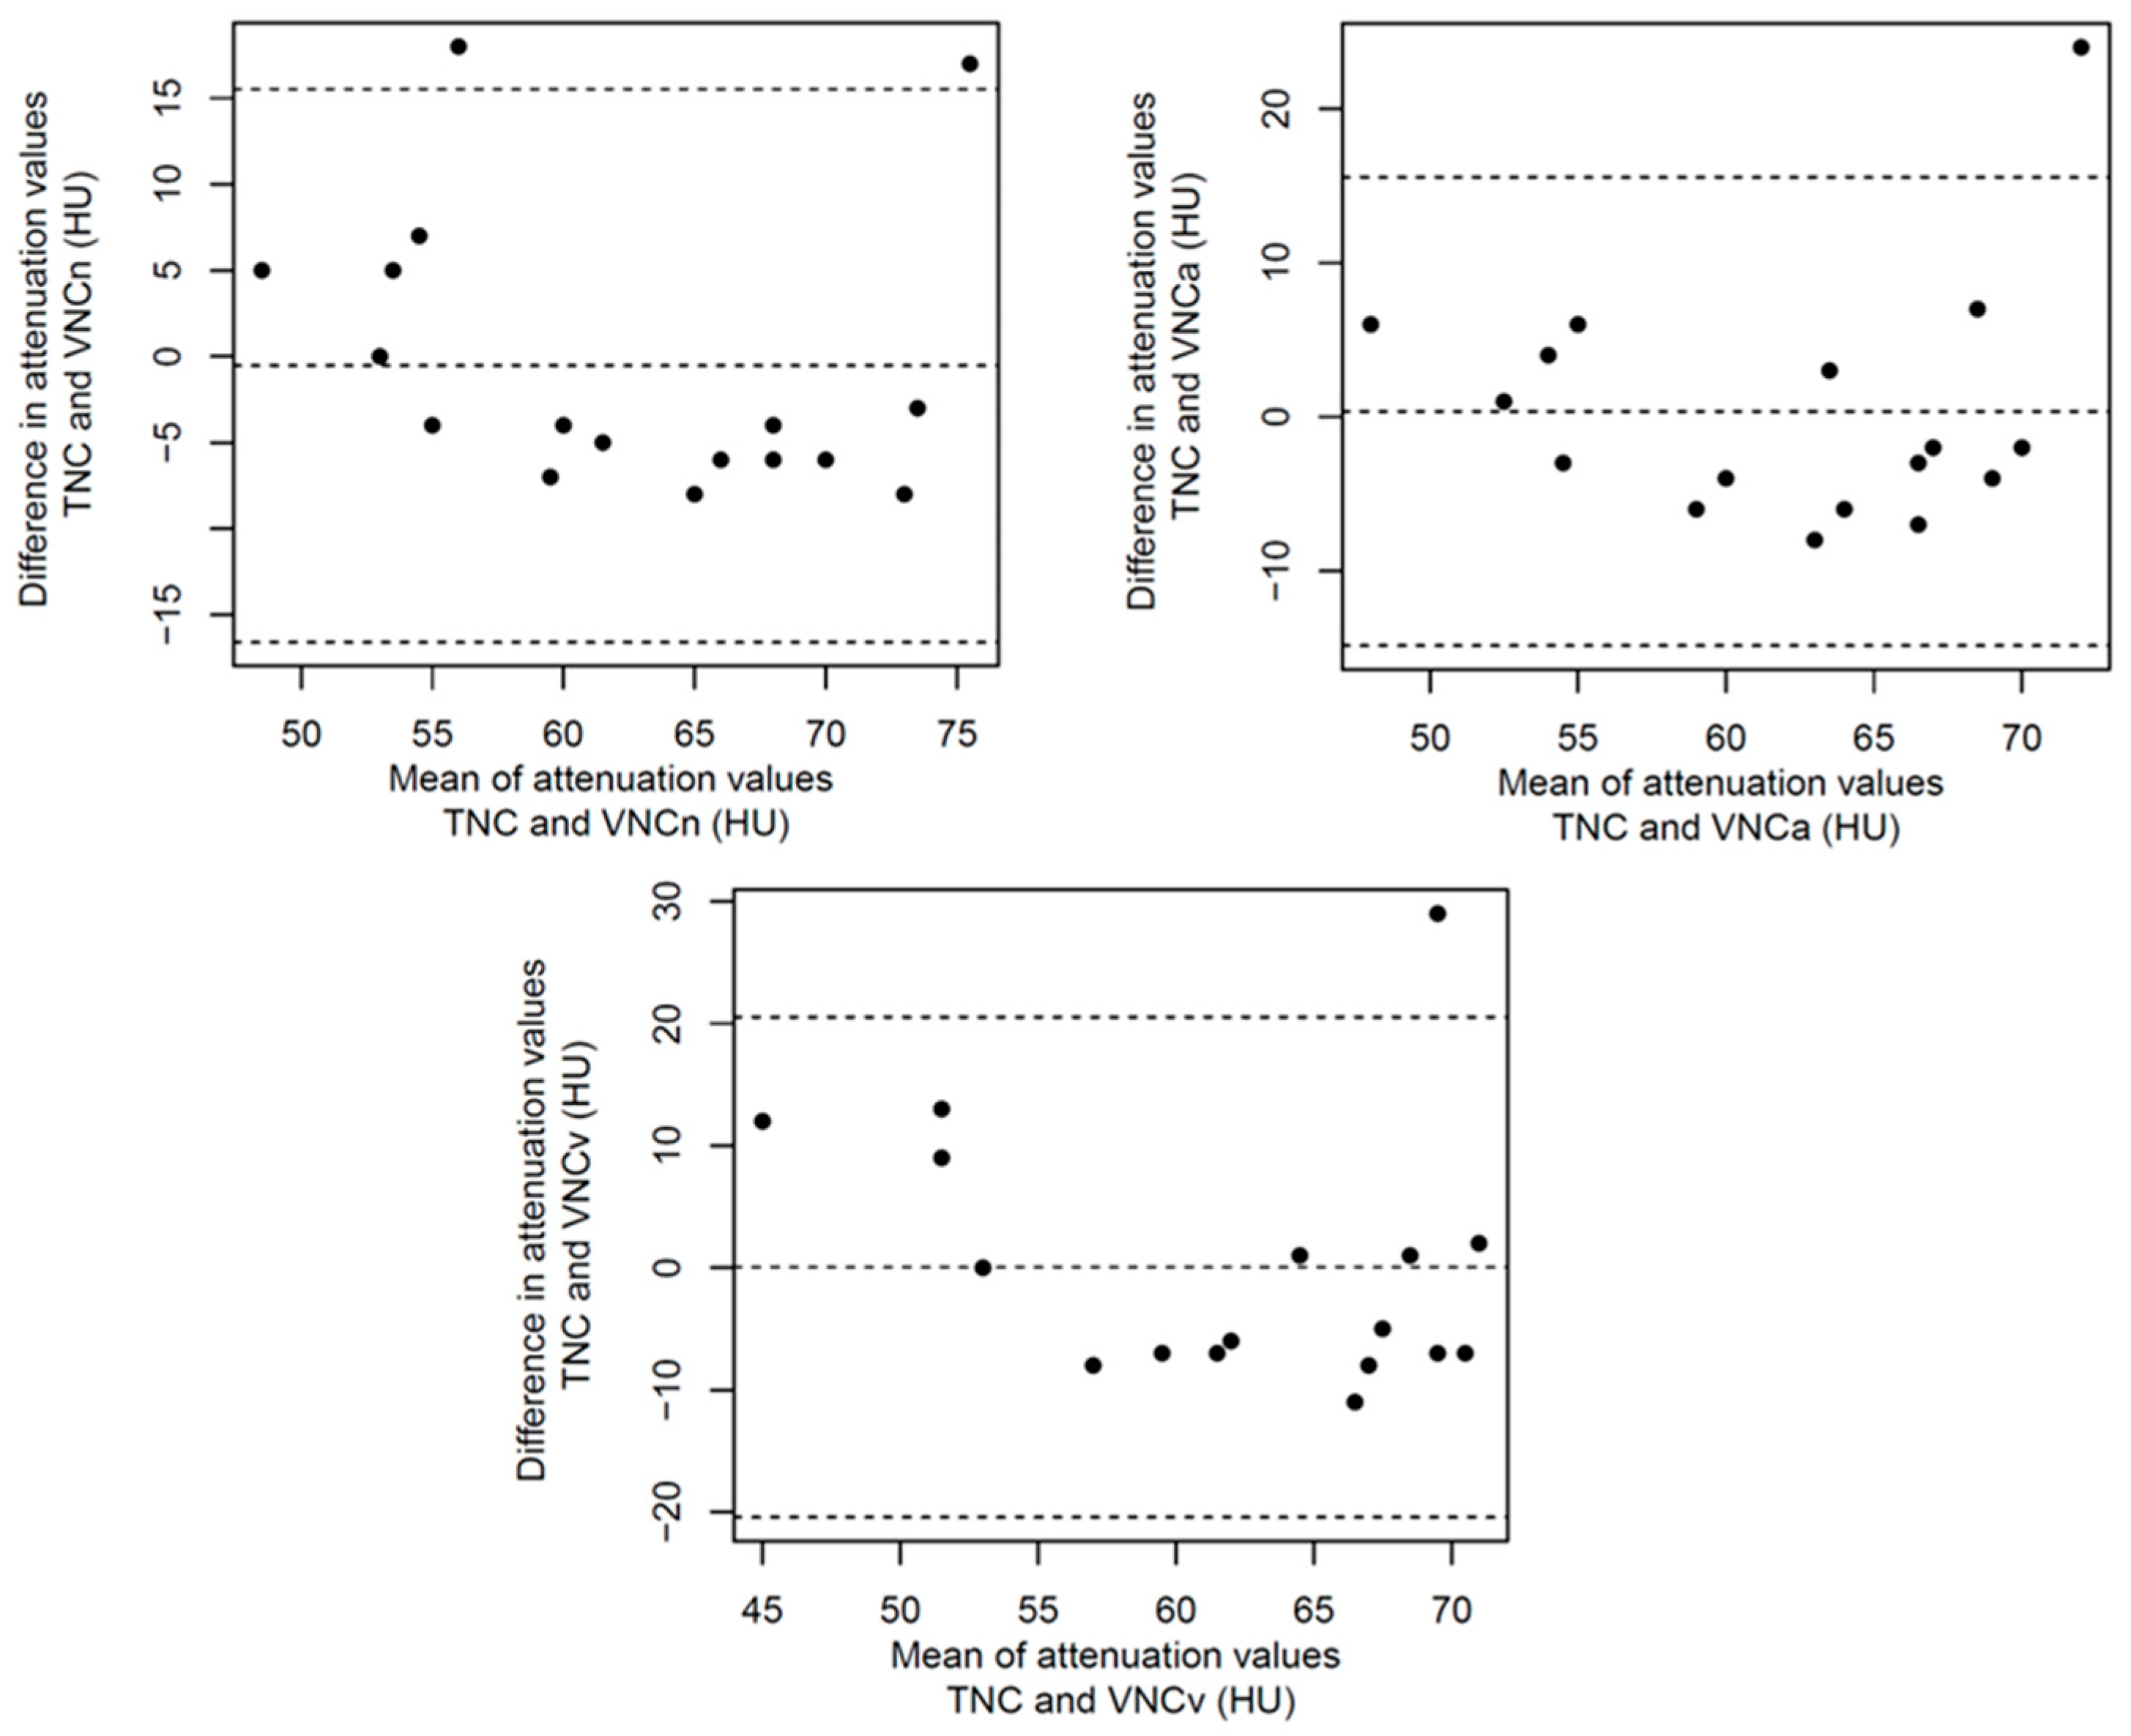

3.2. Structured Measurement